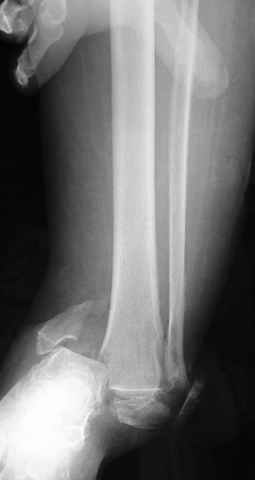

Dear all,40 y.o. man had sustained this terrible fracture falling from a motorbike.

Closed fracture.

This is really Pilon Fx (C3.3; the high energy and the extent of distal tibia comminution are defining it).